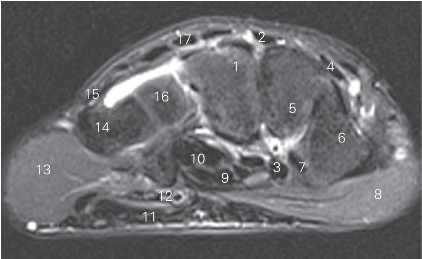

图4-43 经远侧列腕骨远侧份的横断层MR T2WI FS

1 指伸肌腱 tendon of extensor digitorum 2 头状骨capitate bone

3 桡侧腕长伸肌腱 tendon of extensor carpi radialis longus

4 桡侧腕短伸肌腱 tendon of extensor carpi radialis brevis

5 舟骨scaphoid bone

6 拇长伸肌腱 tendon of extensor pollicis longus

7 拇短伸肌腱 tendon of extensor pollicis brevis

8 拇长展肌腱 tendon of abductor pollicis longus

9 拇长屈肌腱 tendon of flexor pollicis longus

10 桡侧腕屈肌腱 tendon of flexor carpi radialis

11 腕管支持带tenaculum of carpal canal

12 指深屈肌腱 tendon of flexor digitorum profundus

13 指浅屈肌腱 tendon of flexor digitorum superficialis

14 尺侧腕屈肌腱 tendon of flexor carpi ulnaris 15 小鱼际hypothenar

16 豌豆骨pisiform bone 17 三角骨triquetral bone

18 尺侧腕伸肌腱 tendon of extensor carpi ulnaris

19 小指伸肌腱 tendon of extensor digiti minimi